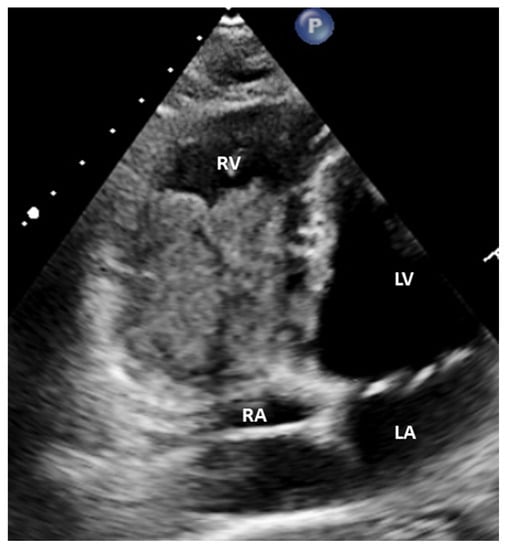

Figure 3. Echocardiogram, modified four chamber view: The tumor in RV has been enlarged occupying the majority of the chamber.

The following supporting information can be downloaded at: https://www.mdpi.com/article/10.3390/diagnostics12030587/s1, Video S1. Apical modified 4-chamber view on transthoracic echocardiography: The tumor in RV has been enlarged occupying the majority of the chamber while the tumor in RA is unchanged.